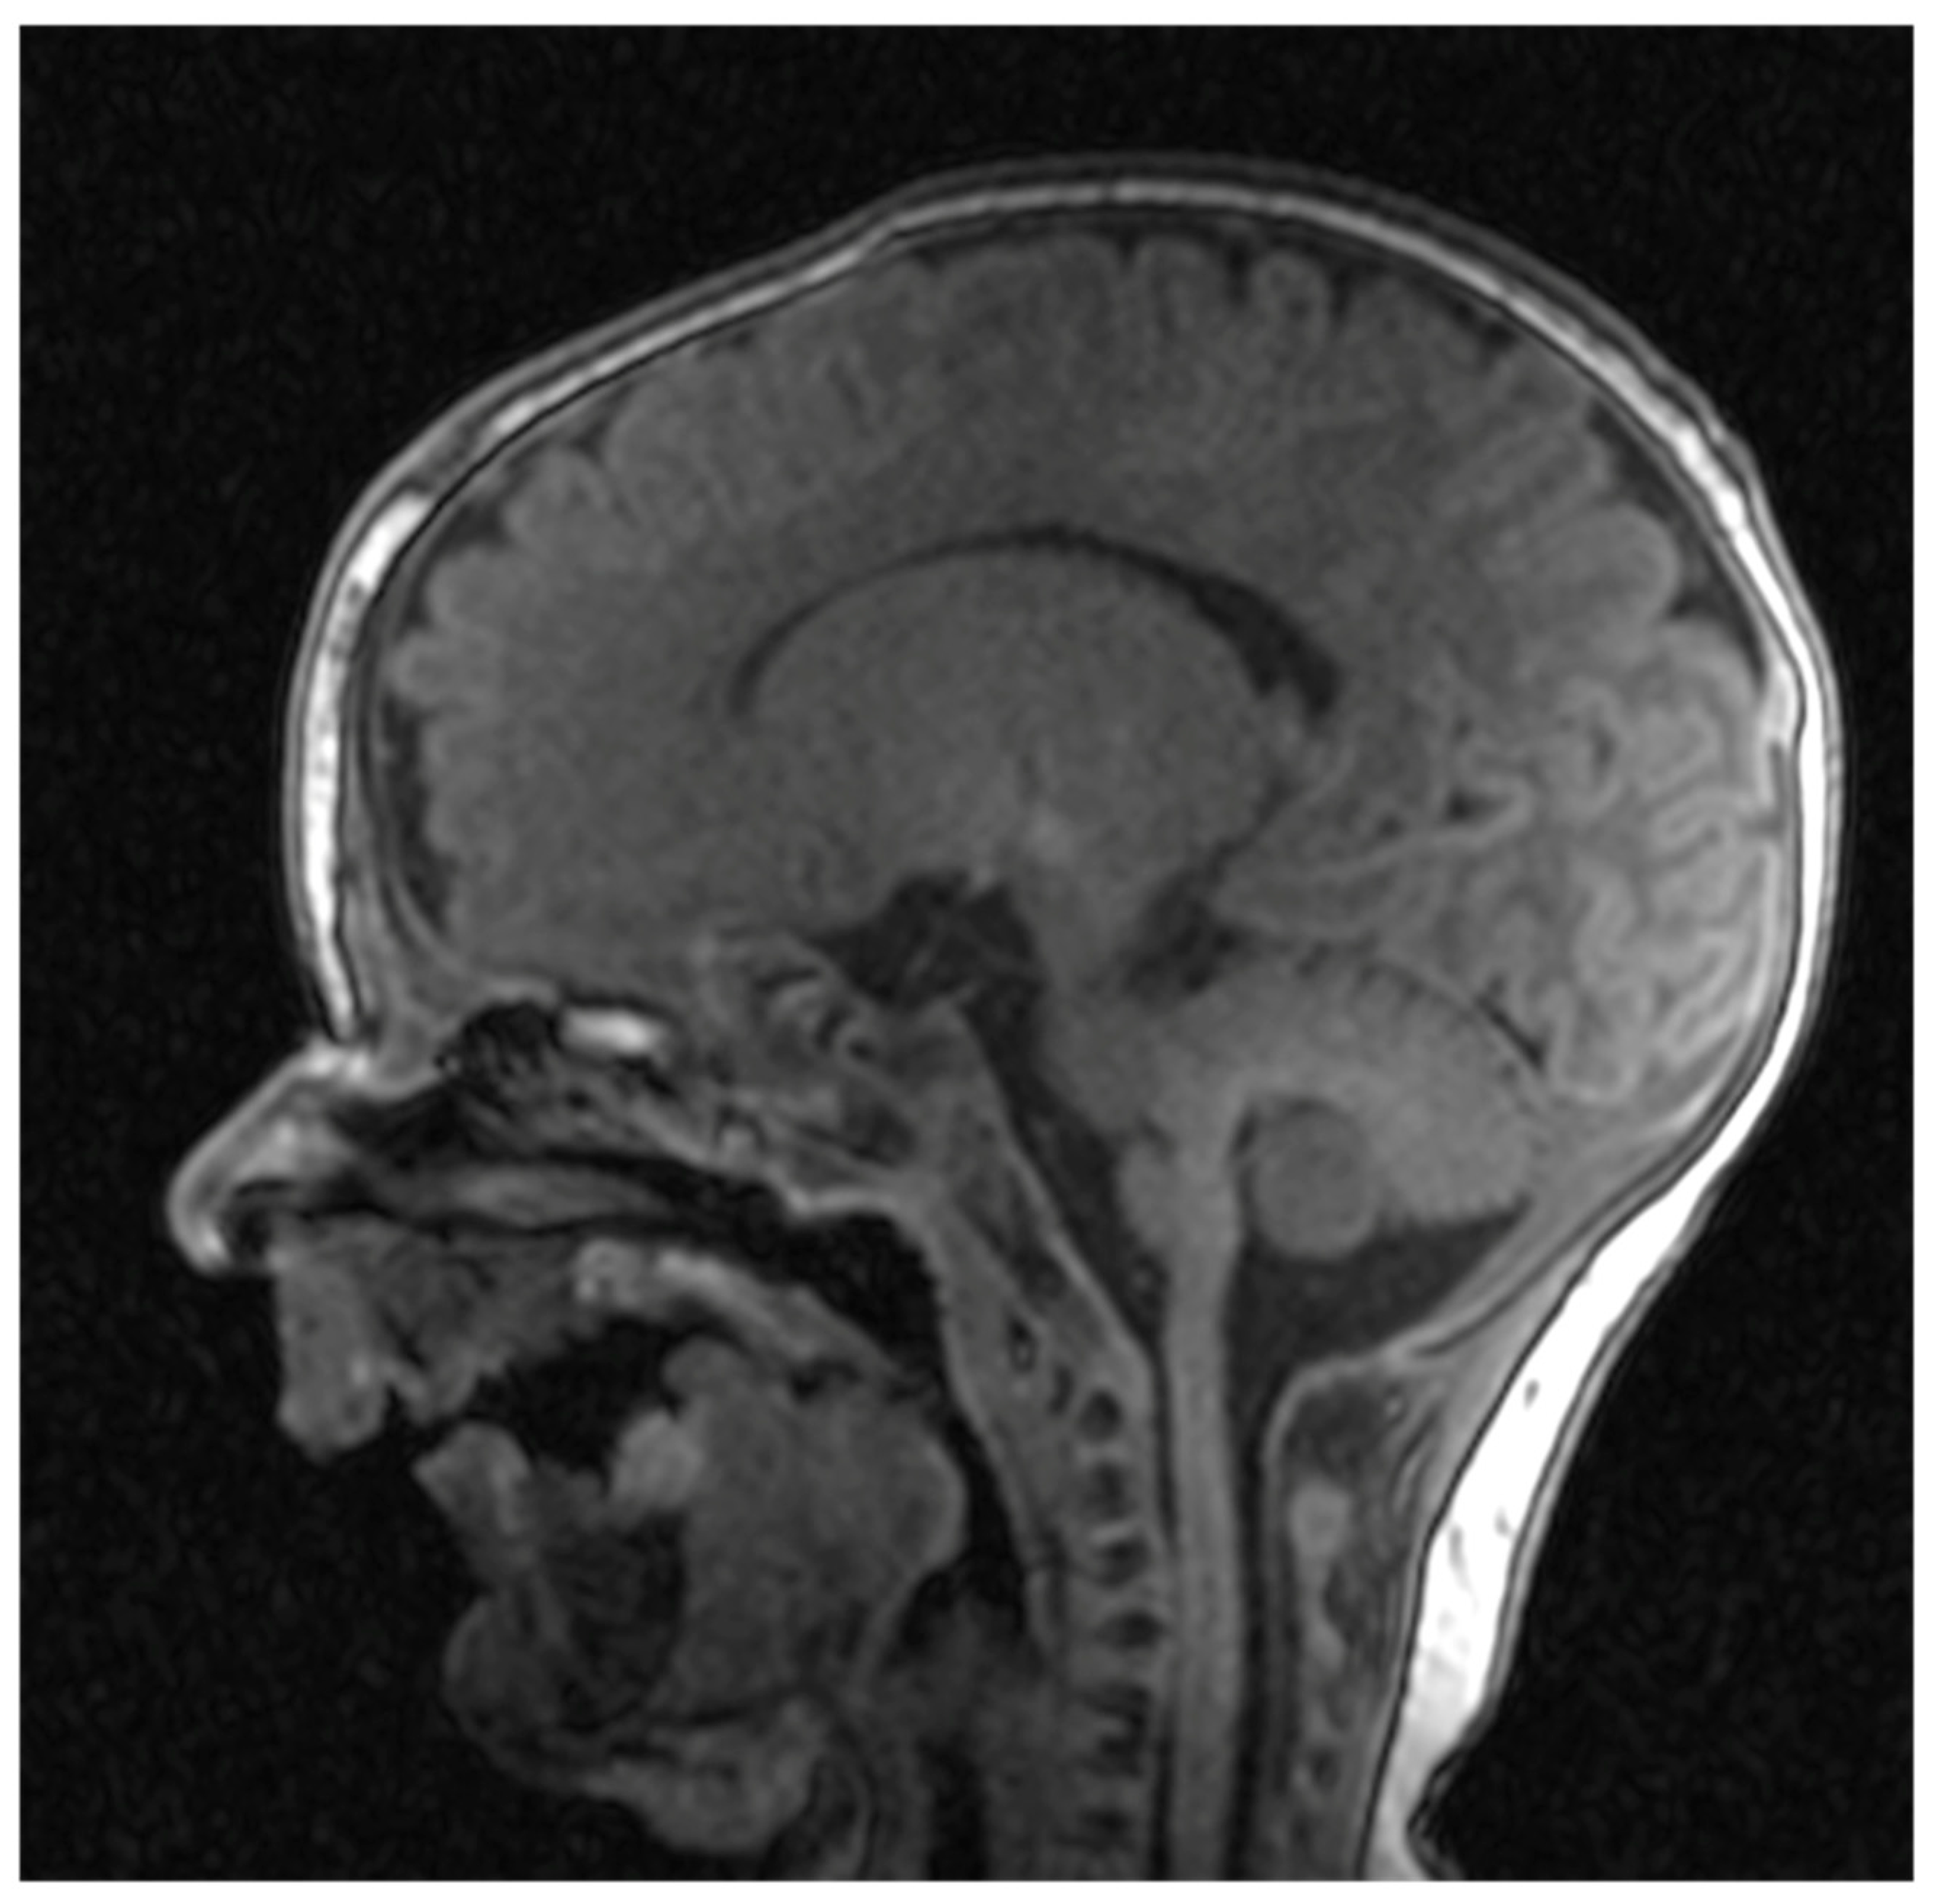

Cranial nuclear magnetic resonance showed no detectable pathological changes in brain structures and tissues. Brain ventricles and extracerebral cerebrospinal fluid spaces had physiological dimensions. Pronounced mycognathia and oral cavity without a developed tongue (Figure 5).

Figure 5. Cranial nuclear magnetic resonance with pronounced mycrognathia and oral cavity without a developed tongue.